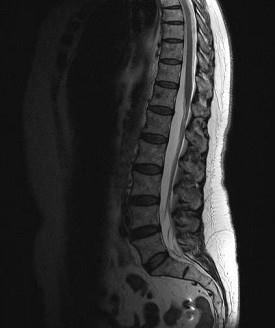

问题 女,57岁,背部隐痛1个月余,请结合影像学检查,选出最可能的诊断 ( )

选项 A、椎体压缩骨折 B、脊椎转移瘤 C、脊椎结核 D、强直性脊柱炎 E、化脓性脊柱炎

答案 B